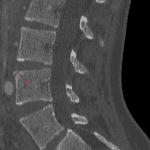

Age: 32

Sex: Male

Indication: Trauma